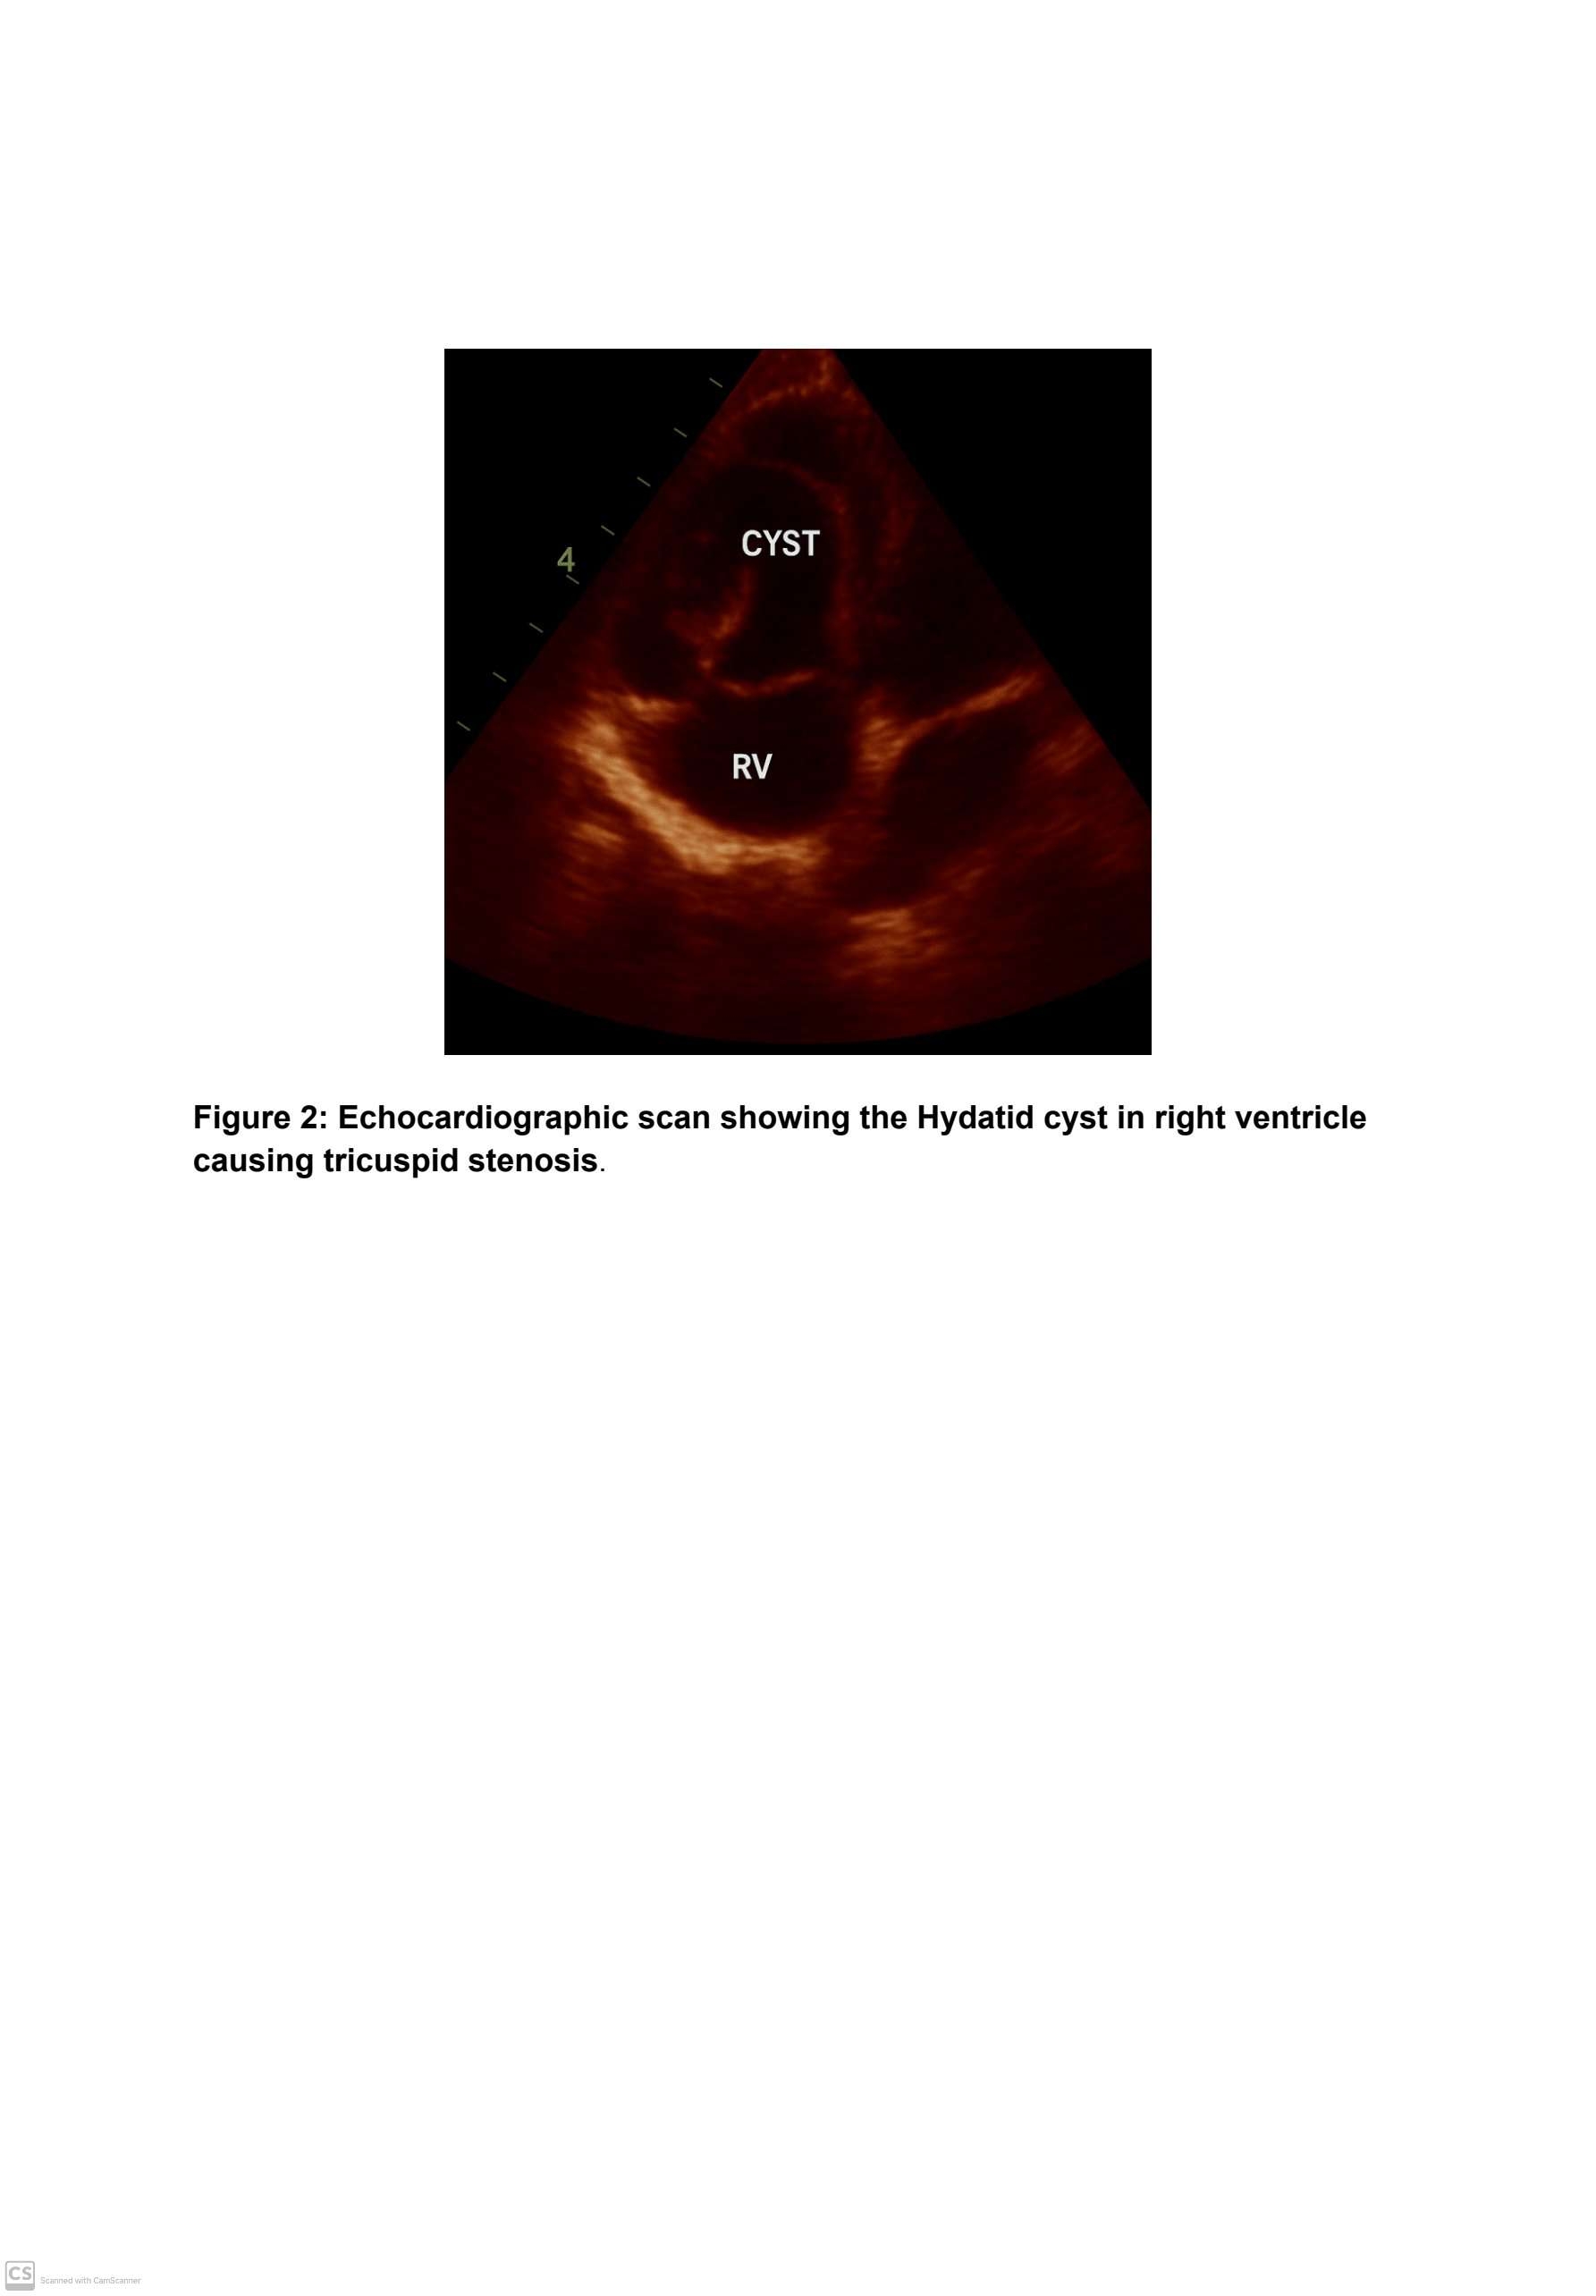

Case Presentation:We report a rare case of a 42-year-old patient who presented to the ED with dyspnea,hemoptysis,chest pain,syncope,peripheral edema,and signs of ight heart failure.On physical examination BP was 100/70 mmHg,heart rate 96 beats/min, and lung auscultation revealed crackling rales, especially on the left. ECG showed abnormal rate and rhythm,and chest X-ray revealed mild to moderate cardiomegaly.Transthoracic echocardiography and cardiac MRI revealed a large,multilocular cystic mass occupying the right ventricle, causing functional tricuspid stenosis. Serology for E.granulosus was positive (ELISA titer 1/1600). After 2 weeks of albendazole therapy (400 mg), emergency cardiac surgery was performed. Under cardiopulmonary bypass, the cysts were carefully excised to avoid rupture. Premedication with midazolam (0.05 mg/kg IV) was administered. General anesthesia was induced with fentanyl (50 µg/kg), thiopental (5 mg/kg), and vecuronium (0.1 mg/kg) for intubation. Anesthesia was maintained with fentanyl (5 µg/kg) and isoflurane. Histopathology confirmed hydatid disease. The postoperative course was uneventful, and the patient was discharged on continued albendazole therapy.

Conclusion:Cardiac hydatid cysts in the right ventricle are exceptionally rare but can be life-threatening. Cardiac involvement is rare as larvae are usually filtered by the liver and lungs; however, some may bypass these organs. The left ventricle is most commonly involved (50%), followed by the right ventricle (20%), interventricular septum (13%), left atrium (9%), right atrium (6%), and interatrial septum (2%). Clinical manifestations vary from asymptomatic to severe heart failure. The number, size, location, and stage of the cyst influence symptoms. Early diagnosis via imaging and serology, followed by timely surgical and antiparasitic treatment, is essential. Hydatid cysts of the right cardiac chambers should be considered in the differential diagnosis of tricuspid stenosis and right heart failure, especially in endemic areas.